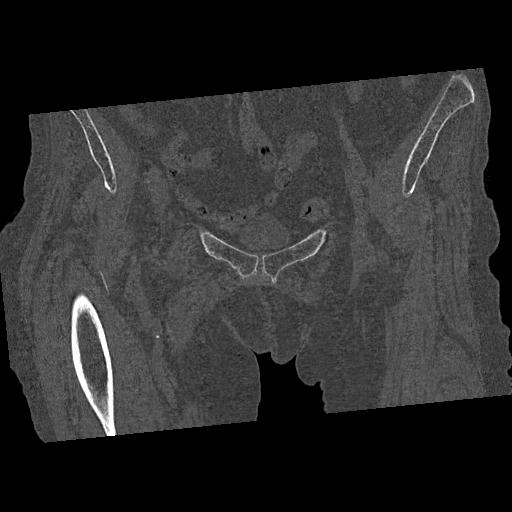

100703 1/27 両股正面+軸 1/29 両股正面+軸 94歳女性 パンソンロン